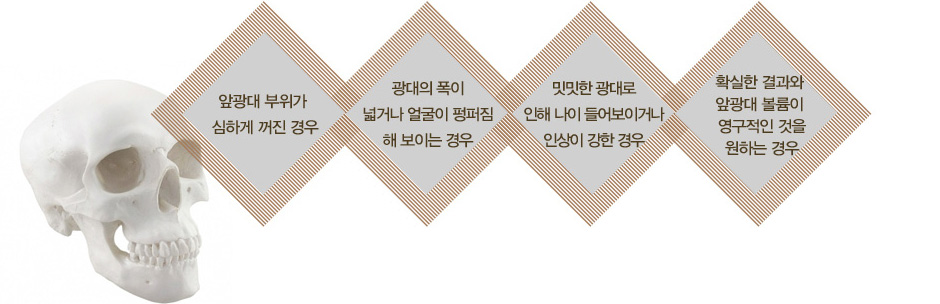

광대의 폭이 넓거나 돌출되지 않으면서도 눈 밑의 앞광대 부위가 볼륨이 없고 밋밋한 경우에는 상대적으로

옆광대가 나와 보이며, 눈 밑 부위가 전체적으로 꺼져 보이고 얼굴이 길어 보일 수 있습니다.

이러한 경우, 자가지방이식 또는 개인별 맞춤 보형물을 사용하여 보다 입체적이며 조화로운

얼굴형을 만들어 줄 수 있습니다.